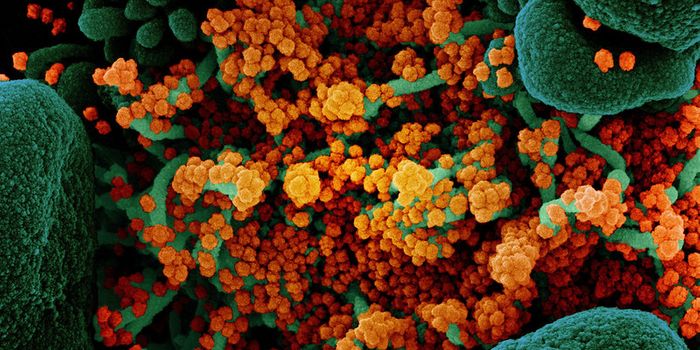

APR 27, 2025MicrobiologyThe SARS-CoV-2 virus that causes COVID-19 emerged to cause millions of deaths and sicken billions of people...

MAR 16, 2025Cell & Molecular BiologyScientists have learned more about how SARS-CoV-2 infections, which cause COVID-19, can ruin the ability of immune cells ...